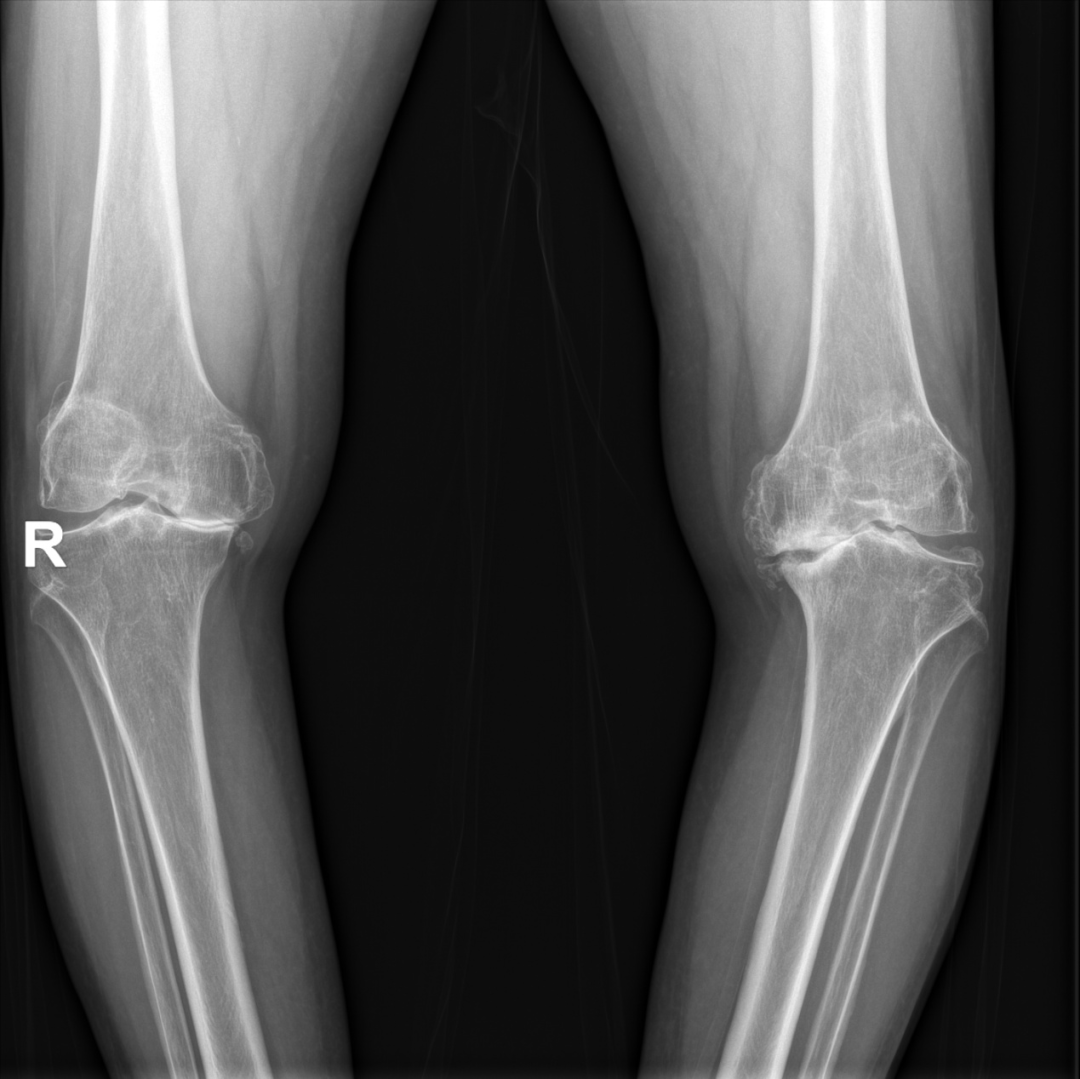

【双膝关节置换,告别多年顽疾】坐着轮椅进医院,自己走着回家